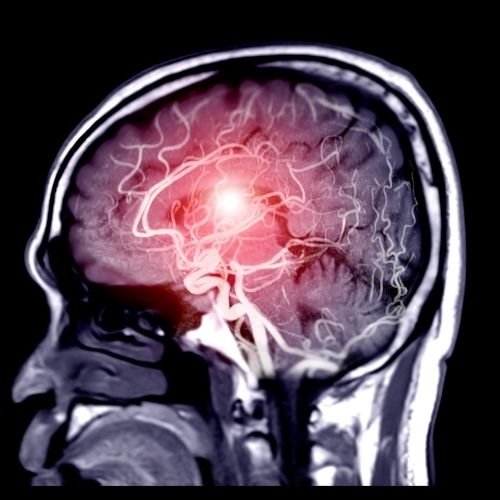

Resonancia Magnética (RM) 3 Tesla

Equipo de RM de 3 Tesla que proporciona imágenes de alta resolución con gran detalle anatómico, sin exposición a radiación ionizante.

Ideal para diagnosticar patologías complejas en cerebro, columna, articulaciones y tejidos blandos, proporcionando imágenes tridimensionales claras.